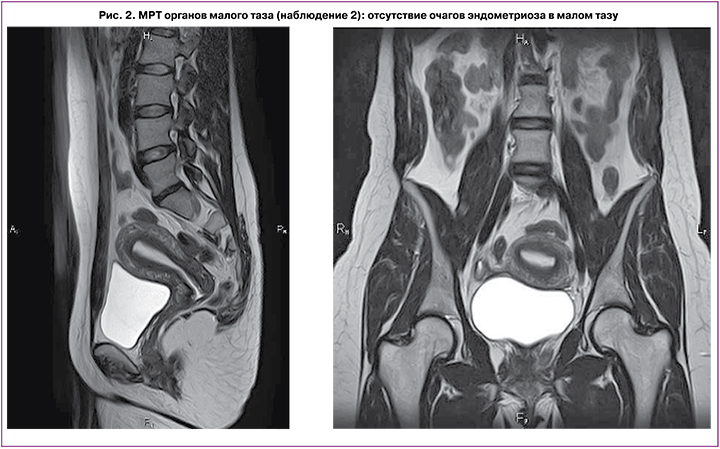

С июня по август 2020 г. (36 лет) впервые возникли рецидивирующие пневмотораксы во время менструации, которые проявлялись одышкой, болями в грудной клетке. Приступы протекали не тяжело и самостоятельно разрешались в течение 2 недель. В сентябре 2020 г. обратилась в ФГБУ «НМИЦ АГиП им. В.И. Кулакова», где был заподозрен ТЭ. Однако, при обследовании, по данным МРТ малого таза, данных за генитальный эндометриоз не найдено (рис. 2), по данным КТ, органов грудной полости признаков пневмоторакса на момент исследования не было выявлено.

Пациентка направлена для дообследования и консультирования к торакальным хирургам. С целью уточнения диагноза пациентке рекомендована торакоскопия, однако в связи с пандемией COVID-19 операция была произведена лишь через 9 месяцев (в июне 2021 г.) в НИИ скорой помощи им. Н.В. Склифосовского в объеме: Торакоскопия, торакальная резекция правого легкого, плеврэктомия. При гистологическом исследовании биоптатов подтвержден эндометриоз плевры. После операции рекомендована терапия аГнРГ (диферелин 3,75 1 раз в 28 дней) и пациентка снова направлена в ФГБУ «НМИЦ АГиП им В.И. Кулакова» для дальнейшего лечения. При повторном проведении МРТ органов малого таза вновь не были выявлены признаки генитального эндометриоза. Гормональное исследование показало снижение овариального резерва (АМГ=0,14), и в связи с настойчивым желанием женщины сохранить генетический материал для дальнейшей реализации репродуктивной функции принято решение воздержаться от терапии аГнРГ после 1-й инъекции. Пациентка направлена к репродуктологу для забора и криоконсервации ооцитов. При проведении программы ЭКО в коротком протоколе было получено 5 ооцитов, витрифицировано 3. В дальнейшем пациентка планирует повторить цикл стимуляции с целью витрификации максимально возможного количества ооцитов, в связи с чем до настоящего времени отказывается от супрессивной гормонотерапии. На этом фоне в сентябре 2021 г. вновь во время менструации предъявила жалобы на одышку и боль в грудной клетке, приступ купировался самостоятельно. С пациенткой проведена беседа о необходимости гормональной терапии прогестагенами (диеногестом) между программами ЭКО и после их окончания с целью предупреждения рецидивов ТЭ.